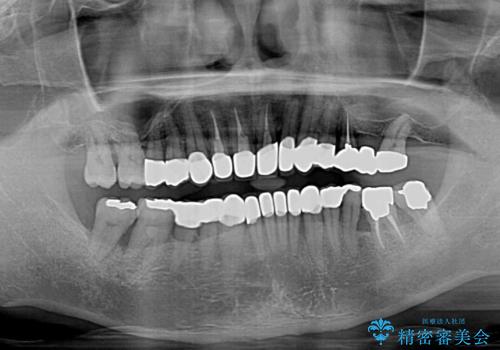

- 幼少期の薬剤の影響で歯が変色していていることを気にして来院された患者様です。

仕事も落ち着き、長年気にしていた前歯の色をきれいにしたいとのことでした。

上下ともに前歯のセラミッククラウンによる補綴治療を希望されていましたが、下顎前歯は叢生が強いため、補綴治療前に部分矯正を行って歯列を整えた上で、補綴治療を行うこととしました。

臼歯部には歯周ポケットのある箇所が散見されましたが、まずは前歯を治療したいとのことで、治療を進めました。

ディープバイトにより臼歯部に負担のかかる咬合であったので、補綴治療後には、矯正治療の後戻り防止もかねて、睡眠時にマウスピースを装着するように指示しました。